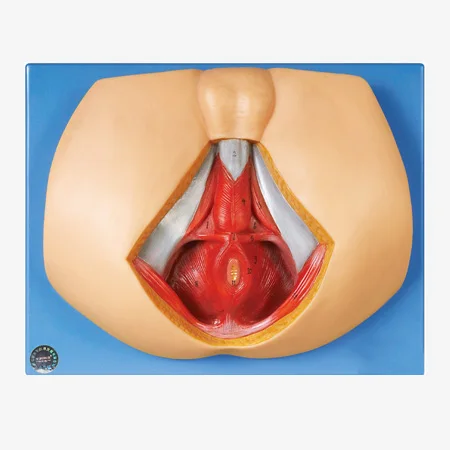

会陰解剖模型 6000 15 Altay Scientific 婦人科治療用 実習用 男性用

男性会陰部解剖学 Buy 会陰解剖学 会陰解剖学 会陰解剖 Product On Alibaba Com

Enovo 男性会陰骨盤筋解剖モデル泌尿生殖器手術 Medical Science Aliexpress